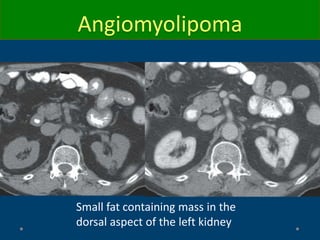

Angiomyolipoma

Small fat containing mass in the

dorsal aspect of the left kidney